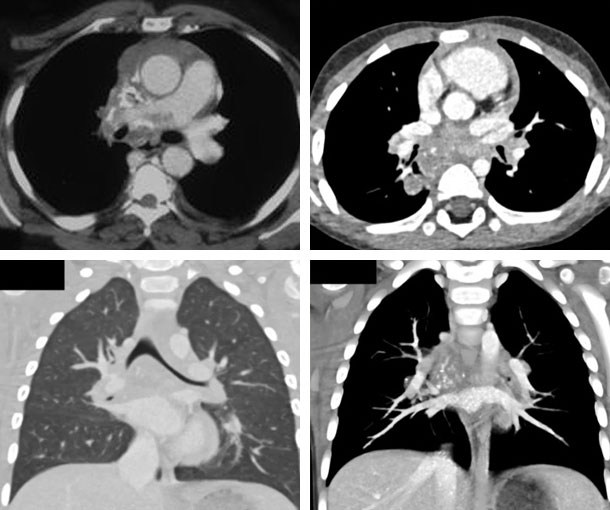

Chest CT Appearances

Histoplasmosis CT Findings

- Diffuse patchy infiltrates in one or several lobes

- Can be solitary or multiple

- Consolidations

- Hilar and mediastinal lymphadenopathy is common

- Nodes may vary in size and can be large

- Ground-glass opacities

- Cavitation

- Central necrosis

- Can calcify over time and become a histoplasmoma

- Can mimic other thoracic diseases